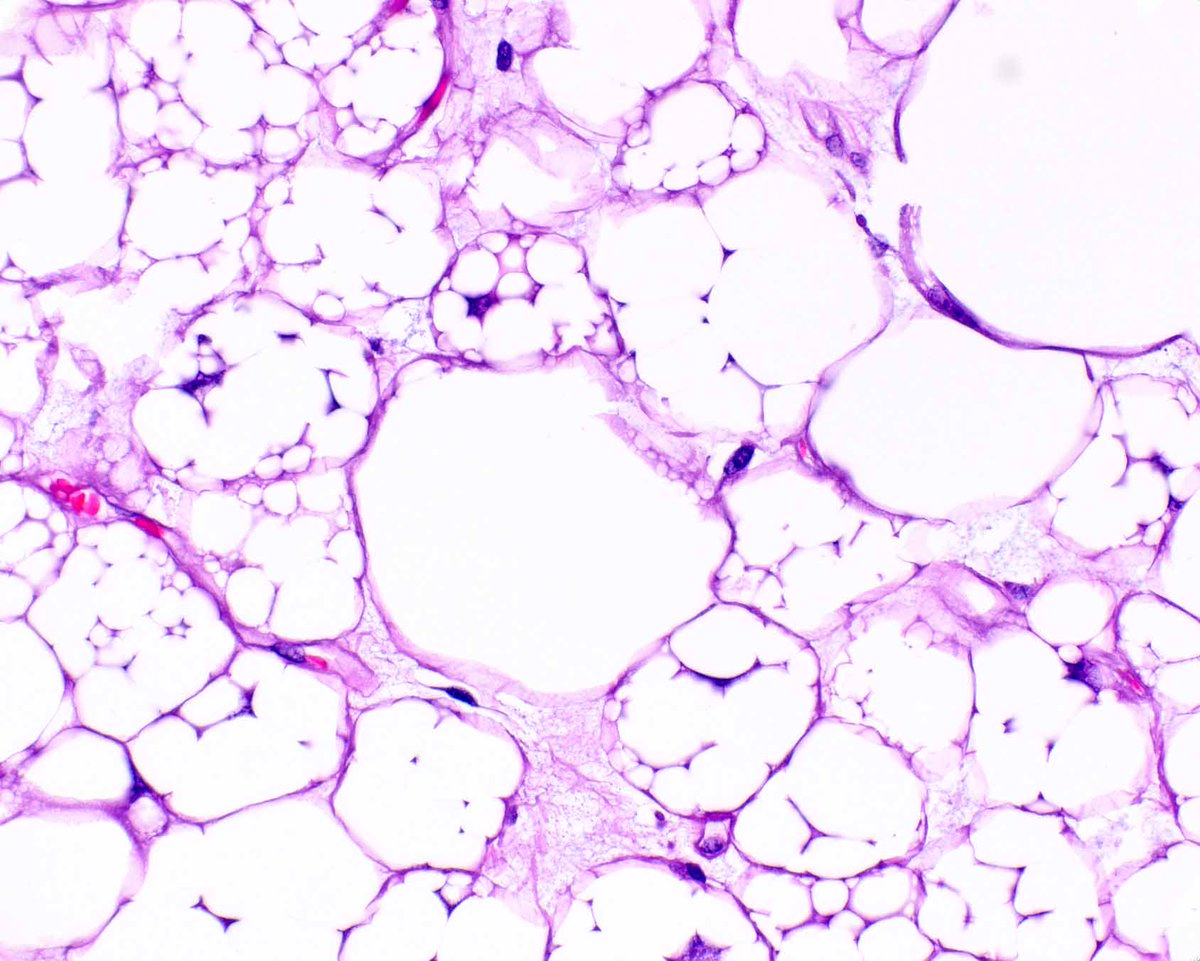

This atypical lipomatous tumor (well-differentiated liposarcoma) is unusual in containing plentiful lipoblasts.